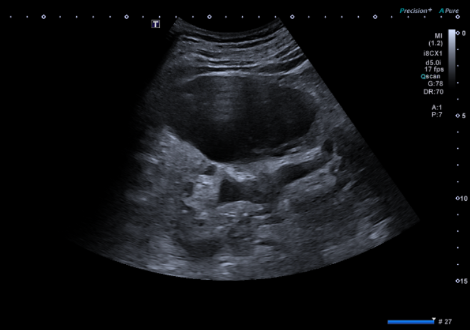

- Ecografía clínica renovesical: Vejiga sin lesiones ocupantes de espacio, sin residuo postmiccional, próstata de tamaño aumentado (56 cc). Ambos riñones con quistes corticales simples, de hasta 9,6 cm en el riñón izquierdo. Sistema excretor derecho no dilatado. Leve-moderada dilatación pielocalicial izquierda. No se evidencian imágenes ecográficas sugestivas de litiasis en pelvis renal.

- Resonancia magnética renal con contraste: hidronefrosis grado II izquierda, secundaria a litiasis obstructiva de 5 mm localizada en el tercio inferior del uréter, inmediatamente caudal al cruce con los vasos ilíacos. Quistes sinusales y simples corticales bilaterales, el mayor de 9,4 cm de eje craneocaudal en el polo inferior del riñón izquierdo. Resto sin alteraciones significativas.

Juicio clínico, diagnóstico diferencial, identificación de problemas

A causa de la hematuria macroscópica, se inicia despistaje de cáncer urotelial. En la ecografía no visualizamos lesiones ocupantes de espacio en vejiga aunque la presencia de células atípicas en orina no nos permitió descartar la posibilidad de tumor urotelial. También nos sorprendió la visualización de quistes de gran tamaño de predominio en el riñón izquierdo. Así mismo, la visualización de dilatación pielocalicial izquierda junto con el inicio de molestia en la zona lumbar izquierda, nos hizo pensar en cólico renal. Por un momento, ante tal variedad de hallazgos, «perdimos la perspectiva» del caso.